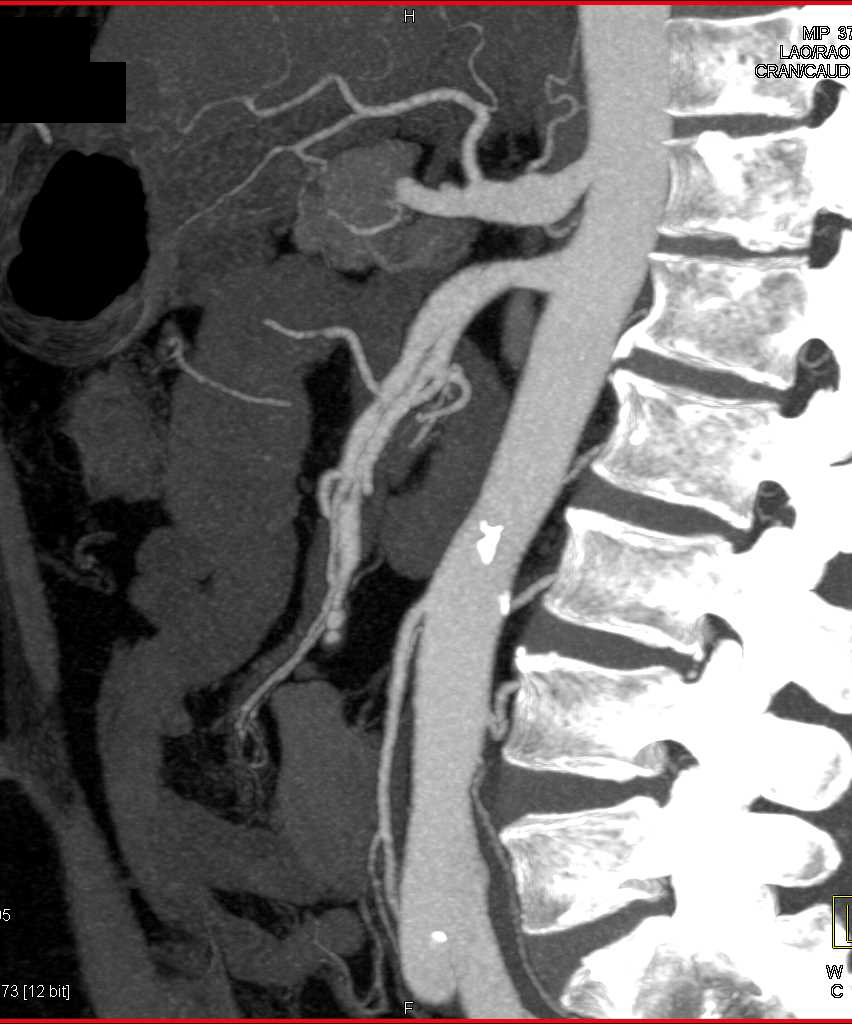

Recurrent Hepatocellular Carcinoma (Hepatoma) Invades the Inferior Vena Cava (IVC)